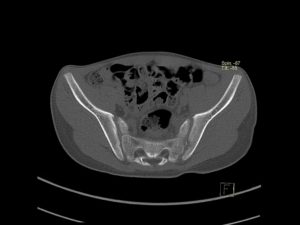

Рентгенологическое исследование костей таза с помощью томографа осуществляется методом многосрезового сканирования. КТ всех костей малого таза является информативным инструментальным диагностическим методом.

С помощью неинвазивного способа обследуются костные и мягкие ткани малого таза. Томограф может сканировать их в трех проекциях, что даёт врачу больше информации.

Главное отличие процедуры от привычного рентгена — сканирование органических текстур человека в трехмерном изображении. Врач выстраивает 3D модель нужного участка организма. Шаг срезов не превышает одного-двух миллиметров, в зависимости от типа применяемого томографа. Высокая точность обеспечивает определение патологии даже при небольшом отклонении от стандартов.

МСКТ суставов и лучевых костей таза в большей степени дает качественное исследование костного аппарата и сочленений. В меньшей мере визуализируются рыхлые участки. На снимке томографии (Кт костей таза) обнаруживаются: